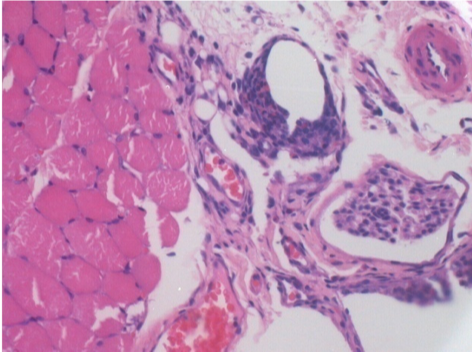

10 Inyección subcutánea

Inyección de endopeel en tejido subcutáneo

0,5 ml (5 x 0,1 ml) Endopeel SC Inyección en el área pretibial subcutánea derecha.

L:200x-Control-SC

R-D10-SC-200X

R-D30-SC-200X

R-D90-SC-200X

R-D210-SC-200X

R-D210-SC-400X

- Endopeel induce una miofibrólisis selectiva reversible y una reacción inflamatoria en un período de 1 mes, aproximadamente

- Los cambios musculares son reversibles casi en su totalidad.

- El músculo es el mejor lugar para inyectar Endopeel debido a su mayor eficacia, control y duración de su acción.

- No se han encontrado necrosis ni abscesos en todo el estudio.